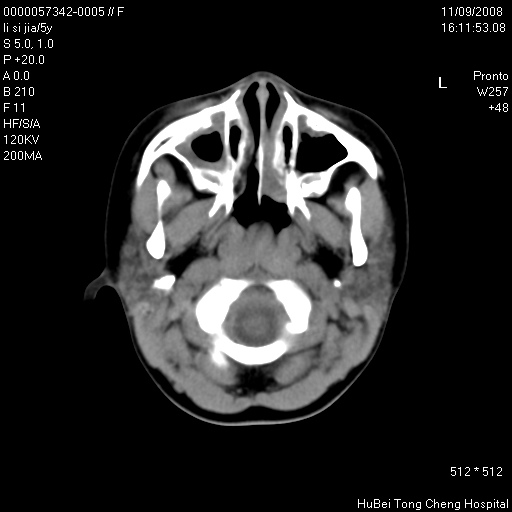

患儿 女,5岁。鼻塞、流涕2年余。

临床诊断:慢性副鼻窦炎?

副鼻窦ct轴位平扫(层厚、层距均为5mm),图像如下:

双侧上颌窦\\筛窦及蝶窦内均可见多量软组织密度影,结合病史支持考虑慢性全鼻窦炎

双侧上颌窦、筛窦及蝶窦内均可见粘膜增厚,结合病史支持考虑慢性全付鼻窦炎,腺样体肥大。